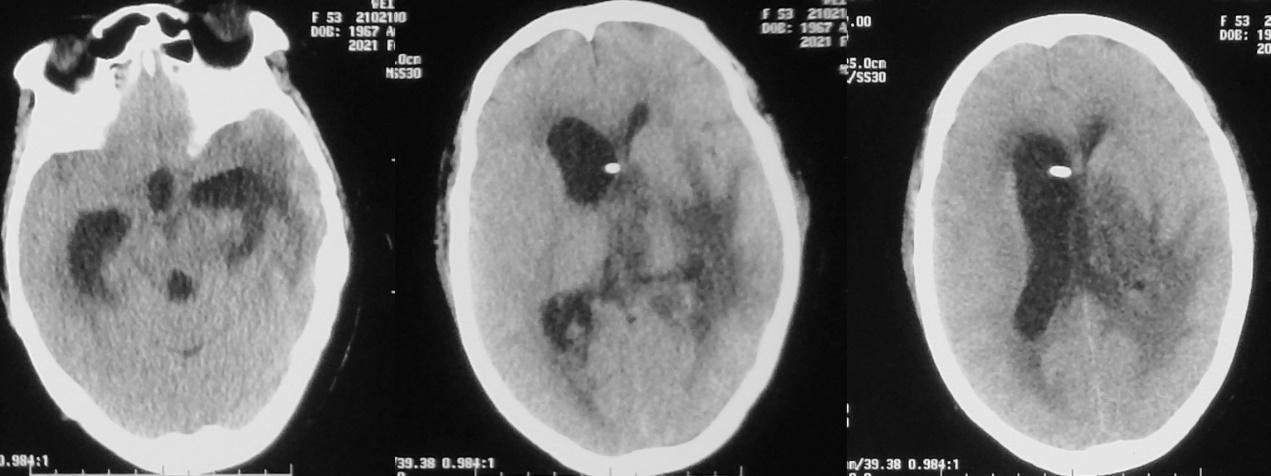

入院当天复查头CT见右侧脑室额角内分流管,脑室扩张;左侧颞角可见外引流管( 图-32 )。

图-32: 2021年2月10日头CT

于入院当天行脑室腹腔分流管拔除+脑室外引流术,同时拔除了左颞角引流管。术后第2天即2021年2月12日,复查头颅CT见引流管位置满意,右侧脑室仍稍扩张( 图-33 )。患者病情平稳,无发热,神志模糊。

图-33: 2021年2月12日头CT

术后第8天,即2021年2月18日,复查头颅CT见右侧脑室缩小,左侧脑室稍扩张( 图-34 )。脑脊液细菌培养结果回报为表皮葡萄球菌,但患者无发热,神志逐渐好转,由入院时的刺痛睁眼好转为可自动睁眼,左侧肢体可遵嘱活动( 图-35 )。

图-34: 2021年2月18日头CT